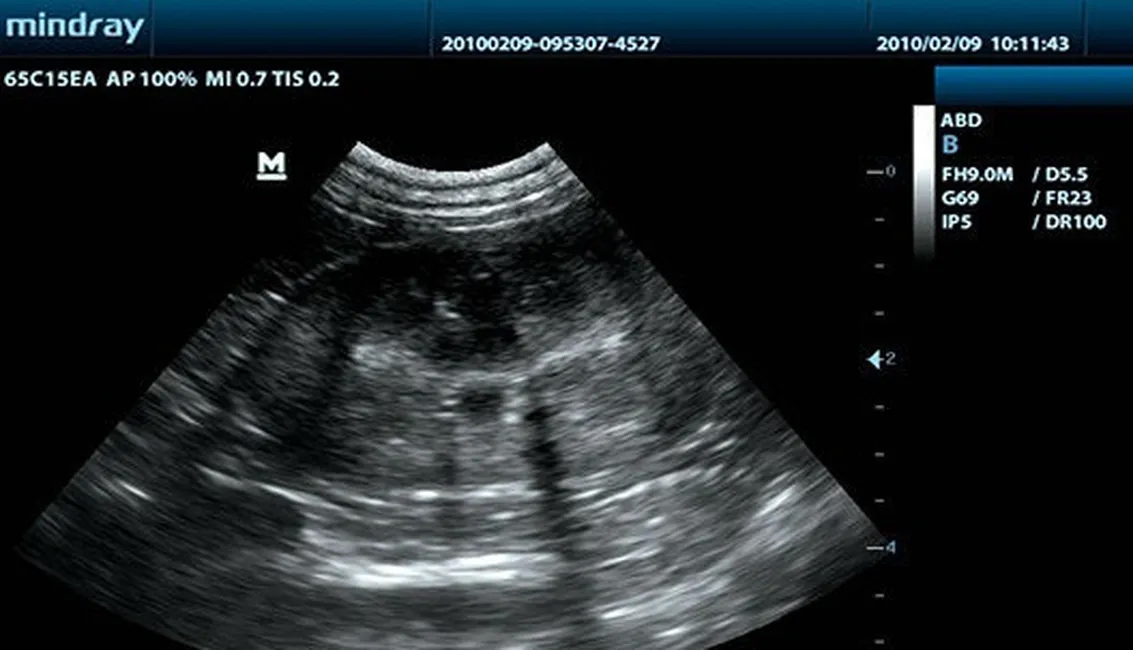

Клинические изображения

Хорошее качество изображения, удобная организация рабочего процесса и незначительный вес являются достоинствами УЗ-сканера DP-10 Vet, черно-белой ультразвуковой системы нового поколения от компании Mindray. С новой платформой, базирующейся на мощном процессоре Intel, УЗИ аппарат обеспечит вам дополнительные возможности ультразвукового исследования.

Используя дополнительные гармоники, генерируемые в тканях пограничных слоев, ТГ значительно повышает контрастное разрешение и улучшает качество изображения, особенно для технически сложных объектов.

Тканеспецифическая визуализация оптимизирует качество изображения в зависимости от свойств исследуемой ткани. Доступны четыре варианта настройки изображения: общие, мышечные ткани, жидкие среды и жировая ткань.